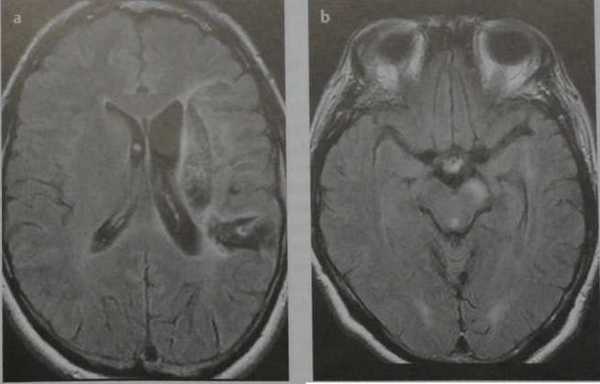

Валлеровская дегенерация вследствие инсульта в бассейне средней мозговой артерии в левом полушарии большого мозга. Р1_А1К-изображения (а, b) и Т2-ВИ в аксиальной плоскости (с). В зоне, кровоснабжаемой левой средней мозговой артерией, визуализируется кистозный дефект с глиозом (а). Определяется повышенная интенсивность сигнала от пирамидного пути в левой ножке мозга (b) и в продолговатом мозге слева (с).